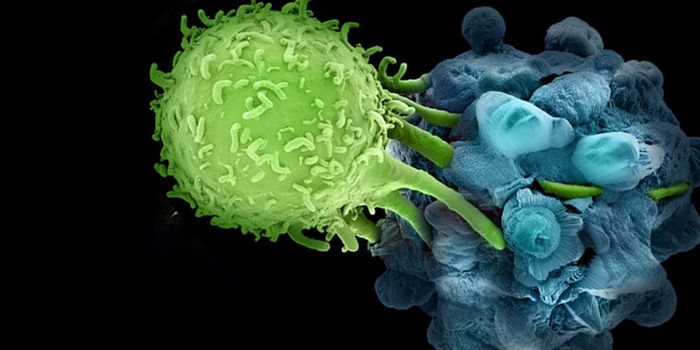

OCT 14, 2016ImmunologyEnhancing a cancer patient’s own T cells to reduce tumor growth is an up-and-coming cancer therapy that is being u ...

NOV 29, 2023CancerThe CAR-T Revolution: Developing T Cells into Cancer Assassins Cancer has long been a formidable foe, but recent ...